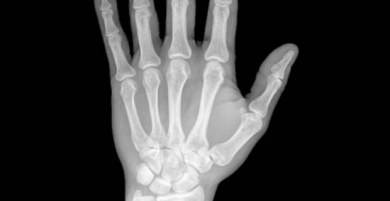

In genere i primi sintomi di questa malattia sono dolori alle estremità con conseguente difficoltà nel muoverle. Questo disturbo è molto più comune nelle persone di età superiore ai cinquant’anni.

L’artrite reumatoide provoca un’infiammazione delle articolazioni e dei tessuti, per questo motivo rende più difficile il normale movimento della rotula. Si tratta di una malattia autoimmune, il che significa che l’organismo attacca se stesso per errore.

Quasi tutte le persone che ne soffrono, lamentano un dolore intenso alle articolazioni, che si fanno più forti la mattina presto. Di solito manifestano anche un calore eccessivo, rossore e deformazione delle articolazioni. Inoltre, sentono mani e piedi intorpiditi, insieme ad altre patologie come la sindrome dell’occhio secco.